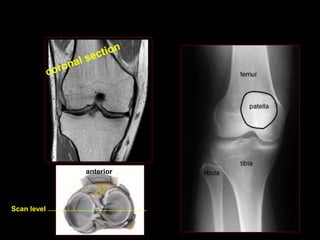

Scan level

anterior

LCA E LCP

LIGAMENTO CRUZADO

-

MENISCI PCL

ACL

MENISCI PATELLA TENDON

MEDIAL

LATERAL

QUADRICEPS TENDON

PATELLA

PATELLAR

TENDON

ANTERIOR CRUCIATE

LIGAMENT

POSTERIOR CRUCIATE

LIGAMENT Scan level